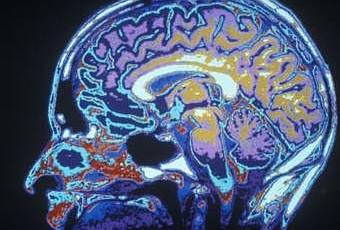

Vemos muchas historias ilustradas con imágenes cerebrales funcionales (fMRI). ¿Qué miden estas imágenes?

La sigla fMRI proviene de functional magnetic resonance imaging o imagen por resonancia magnética funcional y, para hacerla corta, mide dónde se acumula sangre rica en oxígeno en el cerebro, mientras que el subsecuente análisis estadístico intenta decirnos cuán fielmente estos cambios en el flujo sanguíneo están asociados con una tarea mental específica mientras es testeada. Como las áreas más activas necesitan más oxígeno, medir la sangre oxigenada es una manera de inferir dónde se está realizando más “trabajo”.

¿Cuáles son las limitaciones de los estudios de fMRI?

Primero, el flujo sanguíneo no es una gran guía para ver la actividad cerebral – tiende a seguir temporalmente a la actividad neuronal de manera desigual. Segundo, la fMRI no tiene la misma sensibilidad a través de todo el cerebro, es decir, algunas áreas pueden parecer menos activas cuando no lo son. Pero la limitación más importante viene de las dificultades al usar las estadísticas para analizar la enorme cantidad de datos que esta técnica produce. Diferentes técnicas estadísticas pueden producir diferentes resultados. Todas las imágenes del cerebro necesitan más que un poco de interpretación y, a veces, una pizca de sal.